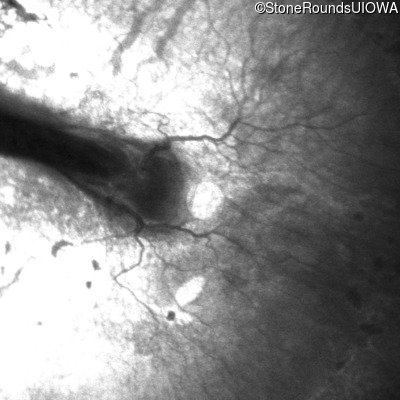

AD Familial Exudative Vitreoretinopathy (IIIE2b)

Age at visit: 23 months

OD OS

This 23 month old male has had nystagmus since shortly after birth. He was born at term (7lbs 12oz).